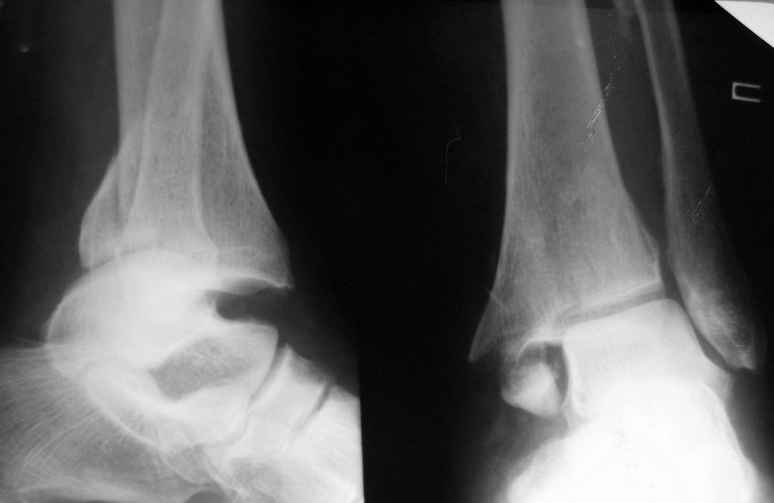

Уважаемые коллеги нужна помощь в определении тактики лечения: Больная Р.,1952 года рождения получила травму 18 августа 2007 года.

31 августа 2007 года была оперирована в другой области по поводу DS Закрытого двухлодыжечного перелома правой голени с подвывихом стопы кнаружи , кзади. Разрыв дистального межберцового синдесмоза. Перелом заднего края большеберцовой кости справа. Поступила в наше отделение со швами ,с некрозом медиальной поверхности правого голеностопного сустава. Проведено : снятие швов , антибиотики , некрэктомия с последующей кожной пластикой .Заживление 20 декабря 2007 года ,выписана из стационара . 3 марта 2008 года поступает с гиперемией , отек , флюктуацией. В настоящее время имеется рана по медиальной поверхности правой голени ,отеки и гиперемия сохраняется .Наша тактика:1) снятия воспалительного процесса, 2) удаление металлоконструкции, 3) выполнения артродеза правого голеностопного сустава.

Алексей20 15 Март 2008, 14:03

Не очень удачный вариант остеосинтеза: сохранен подвывих стопы, синдесмоз не достаточно репонирован. Думаю, в данном случае у пациента д-з: остеоартрит правого голеностопного сустава, послеоперационный остеомиелит правой голени. Предлагаю тактику: одномоментно выполнить удаление металлоконструкции, хирургическую обработку очага остеомиелита, резекцию голеностопного сустава, артродез аппаратом. Другие методы лечения не привидут к купированию гнойного процесса. Так как полость сустава в настоящее время имеет вид пиогенной капсулы, в которой будет поддерживаться гнойный процесс даже после заживления свища, с последующим его открытием и опорожнением гноя.